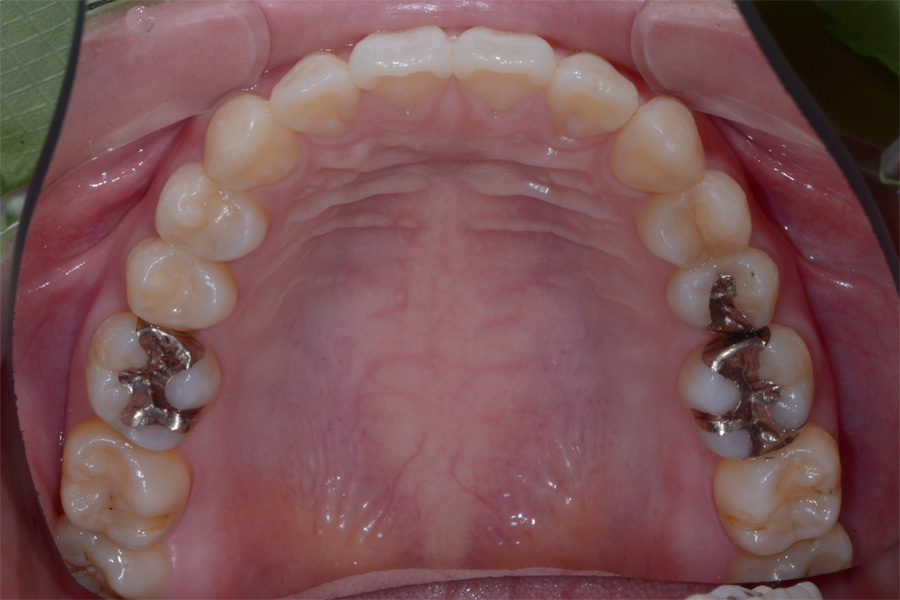

治療後

主訴 出っ歯とすきっ歯を治したい

期間 5か月

費用 20万円(別途調整料)

治療内容 上顎ラビアル矯正(表側矯正)